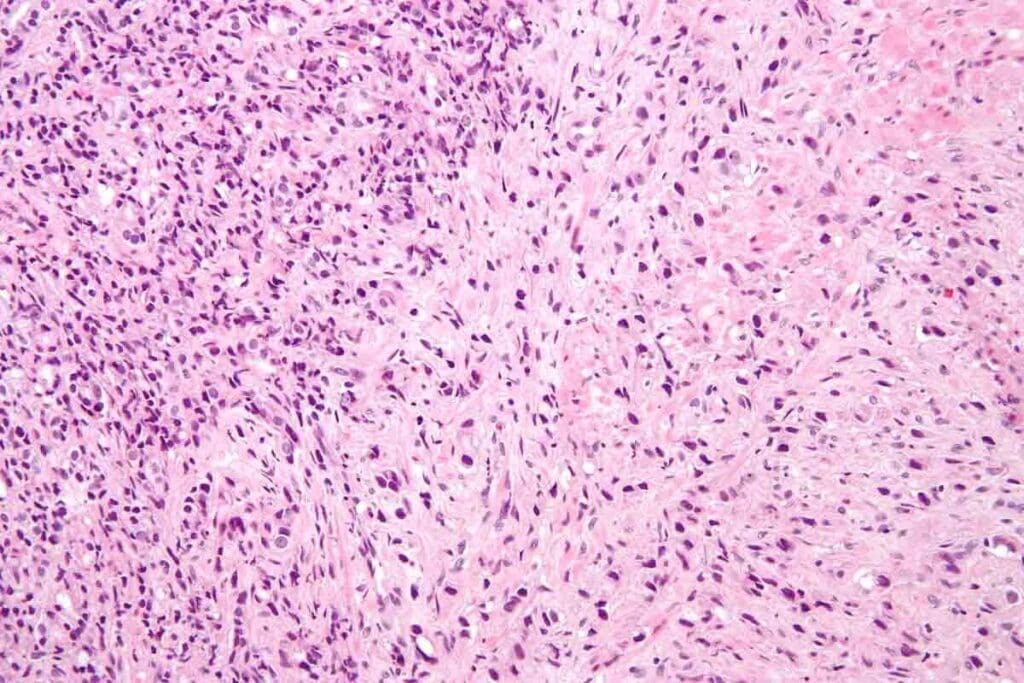

Soft tissue sarcoma is a rare cancer that starts in tissues like fat, muscle, and blood vessels. There are over 50 types, each with its own features. Common ones include liposarcoma, leiomyosarcoma, and undifferentiated pleomorphic sarcoma.

These cancers can develop in different tissues. For example, liposarcomas start in fat tissue, and leiomyosarcomas begin in smooth muscle cells. Knowing the type of sarcoma helps doctors choose the best treatment.

Biopsy Procedures and Definitive Diagnosis

A biopsy is the key to diagnosing soft tissue sarcoma. It involves taking tissue from the tumor for examination. There are different biopsy methods, each suited for different tumor locations and types.

The biopsy sample is studied under a microscope to identify cancer cells. This helps us understand the tumor’s characteristics and plan treatment. Advances in biopsy techniques have improved our ability to tailor treatments to each patient’s needs.